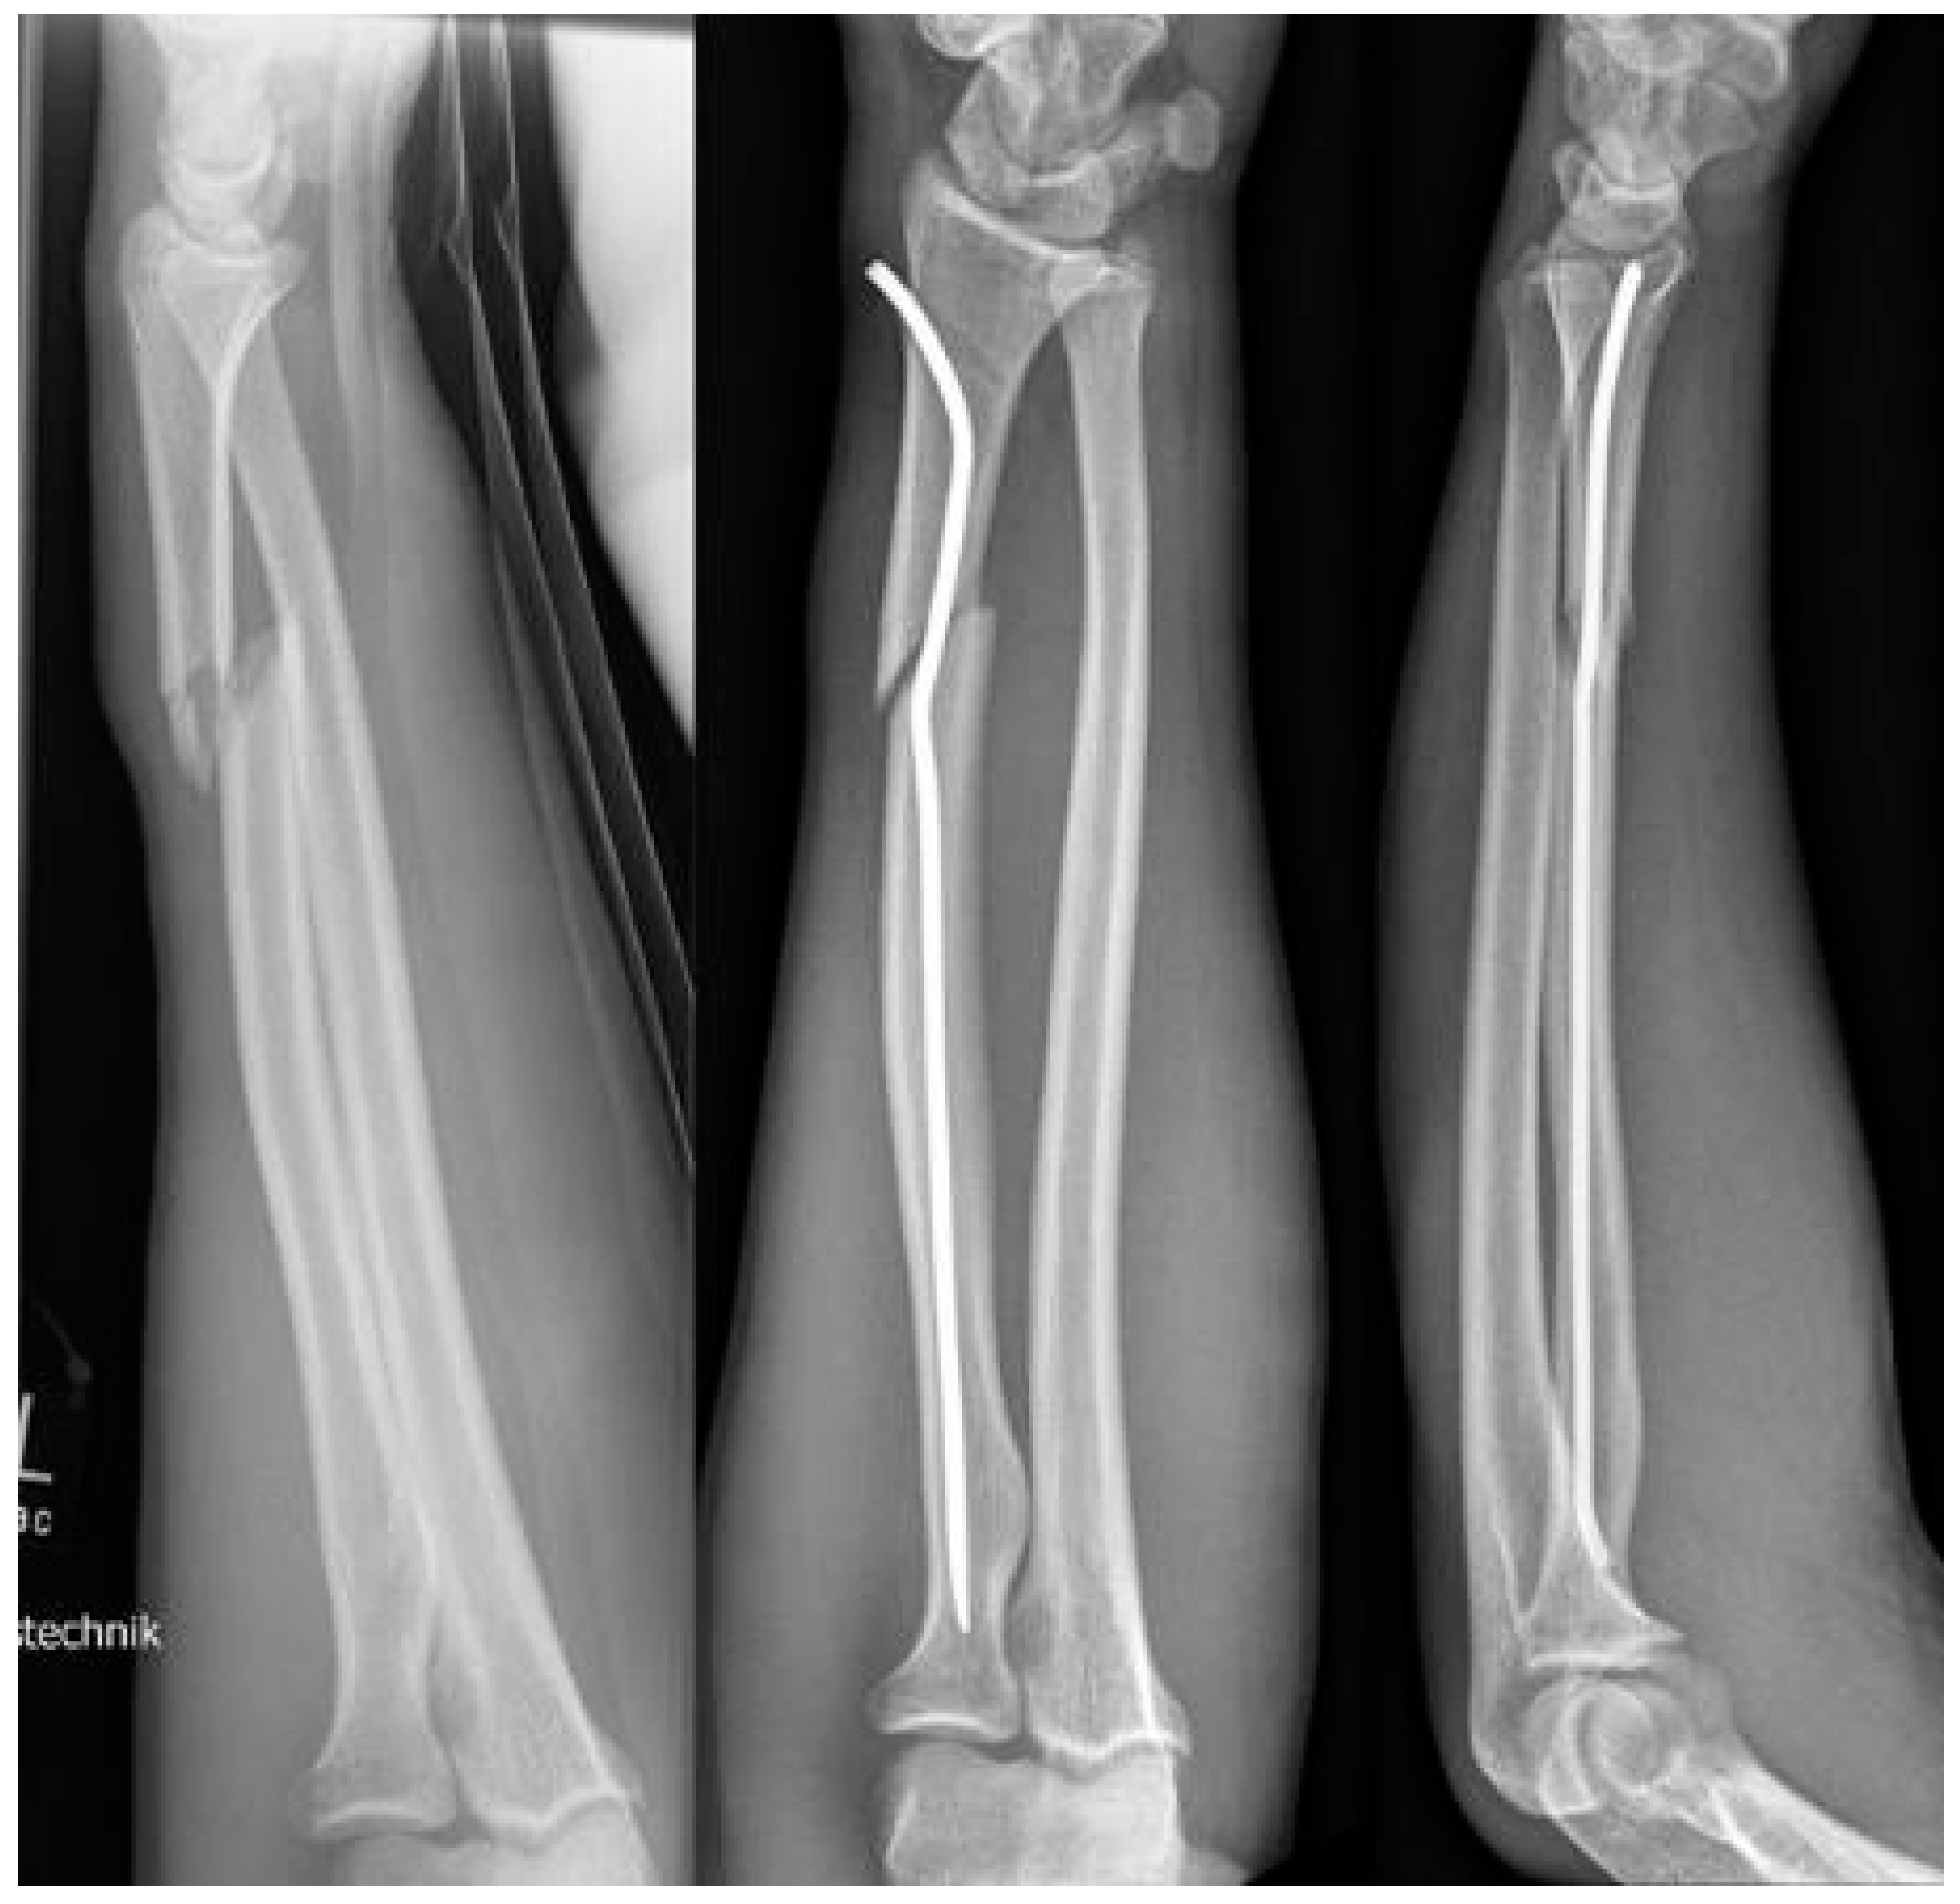

Intramedullary nails, however, if not pre-bent, usually lead to an unacceptable radial displacement of the distal fragment, which makes the situation sometimes worse than it was before (Figure 1). Pre-bending techniques have been described with a single kink, which is placed distal to the fracture, but these remain controversial due to lack of stability [3,10,11]. The same applies to unconventional techniques, such as locked wires [12].

The idea that this new surgical technique is based on is that, if a normal intramedullary nail being brought into the radius from the radial side of the distal radius, displaces the distal fragment radially, the solution would be to insert the nail from the ulnar side, which, however, is not possible, because this area cannot be accessed due to the close anatomical neighborship of the distal ulna. This makes it necessary to simulate an ulnar access. Therefore, the proximal (first) kink of the nail, which at the end of the procedure is placed proximal to the fracture, will push the radial corticalis of the proximal fragment radially, whereas the second kink (which can also be performed as a bend, see Scheme 1) pushes the distal fragment into an anatomical position and makes it possible for the nail to be brought into the distal radius using the established approach. If the entry into the bone is performed exactly with the diameter of the nail, stable osteosynthesis with three-point support is achieved (Figure 1).

Figure 1. Intramedullary nailing without pre-bending of the radial nail leading to a radial displacement of the distal fragment whereas double pre-bent nail ensures three-point support.